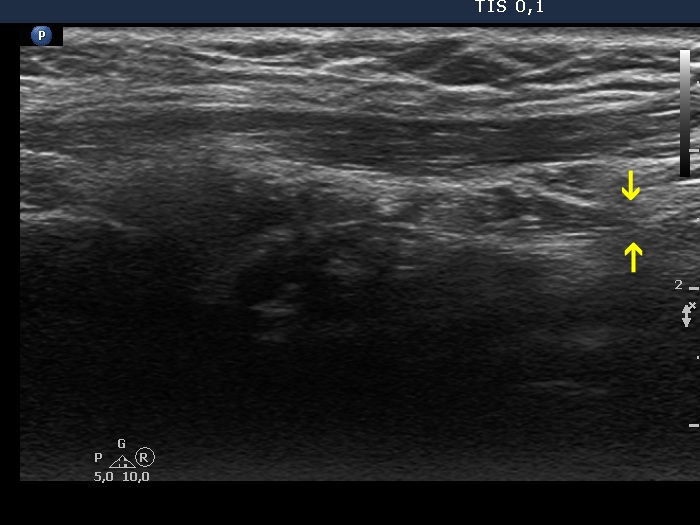

The operated thyroid - case 337 (ultrasonographic picture 7b)

Left lobe, another longitudinal scan. The hypoechoic mass has upper and lower (yellow arrows) tails which means that this does not correspond to thyroid tissue but to muscle fiber.